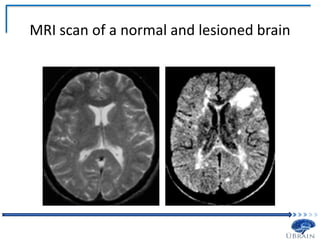

C. Lesions

• Logic: if a brain structure contributes to a task

performance in that task.

so human neuropsychology requires patients with

MRI scan of a normal and lesioned brain